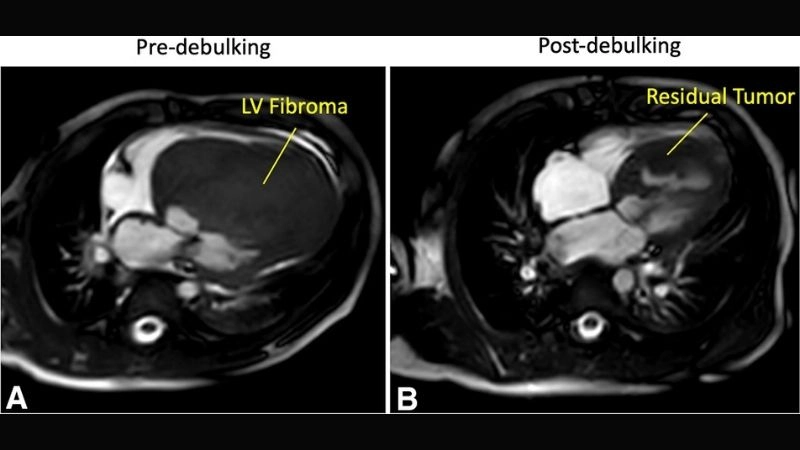

Cardiac fibroma is a rare, benign tumor of the heart composed mainly of fibrous tissue. It often develops in children and may cause symptoms related to heart rhythm and pumping function.